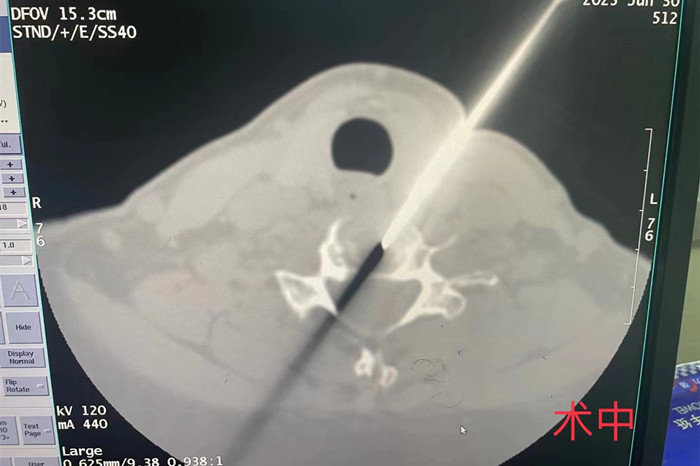

近日,我院疼痛科在南区影像科的配合下,成功开展了首例CT介导经皮穿刺颈椎间盘等离子射频髓核消融手术。

手术由安徽医科大学第一附属医院疼痛科主任王立奎和我院疼痛科副主任耿天勇共同主刀,在南区影像科医师的密切配合下,通过CT引导的精准定位,将细至0.9毫米的等离子射频针穿刺进入患者的病变椎间盘,成功对病灶部位进行射频消融,手术历时1小时左右。术后患者双上肢疼痛麻木即得到明显改善。